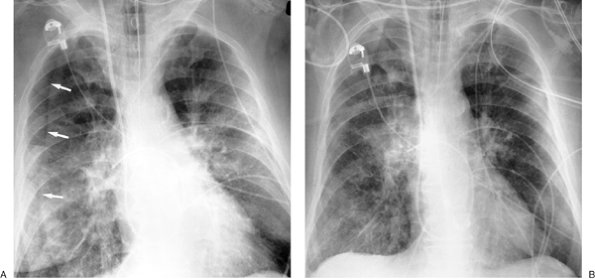

FIGURE 9-12. Re-expansion pulmonary edema. A: PA chest radiograph of a 78-year-old woman with metastatic breast cancer shows a large left pleural effusion associated with collapse of the left lung and shift of the mediastinum to the right. These findings suggest tension hydrothorax. B: PA chest radiograph after placement of a left chest tube and adequate drainage of pleural fluid shows re-expansion pulmonary edema on the left.